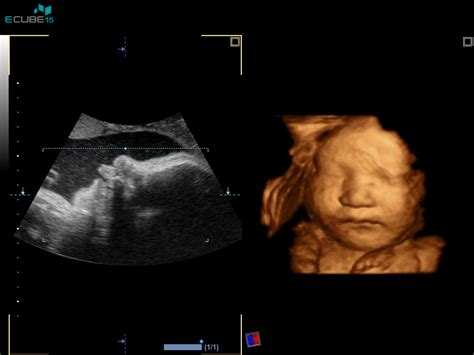

Če je nosečnica zdrava in če je vse v redu, potem v drugem trimesesečju ni "nič posebnega", pravi ginekolog in porodničar dr. Darko Gregorač. "Nosečnica ima lahko spolne odnose, živi naj normalno, naj hodi, telovadi, plava, uživa v prostem času, paziti pa mora, da se s čim ne preobremeni." V tem času je lahko zelo zahrbtno vnetje slepiča, ki je med nosečnostjo običajno prikrito in ga je težko določiti. Nevaren je lahko za mater in otroka. "Če je treba operirati, operiramo," pravi dr. Gregorač, vendar poudarja, da vselej obstajajo nevarnosti komplikacij. "Sama anestezija ni nevarna." V tem času se tudi že lahko pokažejo morebitne razvojne napake pri zarodku, ki jih odkrijemo z ultrazvokom. Poškodovan je lahko vsak organski sistem, zato stalno pregledujemo otrokovo stanje.

Po 36. tednu nosečnosti se izmeri krvni tlak, pregleda urin, po potrebi kri, nosečnica se stehta in pregleda prisotnost oteklin na nogah. Bolj, ko se bliža konec nosečnosti, bolj pogosto je otrdevanje trebuha. Trd trebuh se mora ločiti od pravih popadkov. Če otrok veliko brca, pred 40. tednom ni treba snemati CTG-ja (neprekinjeno elektronsko spremljanje plodovih srčnih utripov in napetosti trebušne stene). Vaginalni pregled se opravi samo po potrebi - v primeru, da žensko tišči navzdol ali da krvavi oziroma ima sluzast izcedek. Pri 36. tednu se preveri lega ploda.